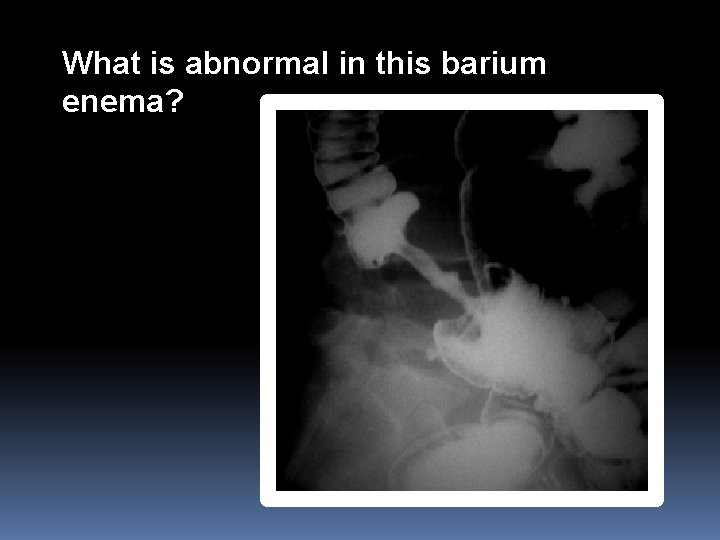

BARIUM ENEMA

What is abnormal in this barium enema?

Colon mass/malignancy (Apple core appearance)